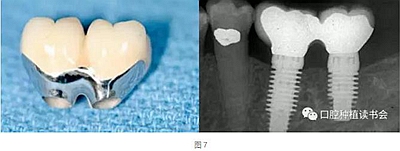

天然牙的預(yù)備通常限制刃狀邊緣的使用以避免最終修復(fù)體外形過凸。沒有具體的研究表明凹形邊緣完成線比其他的完成線形態(tài)更優(yōu)越,但易于預(yù)備的特點(diǎn)是選擇它們的理由,而且避免了修復(fù)體過大。修復(fù)學(xué)中存在幾種常見的刃狀邊緣預(yù)備的適應(yīng)證,因?yàn)樗鼈冎恍枰獦O小的切削量。適應(yīng)證包括:①種植體基臺(tái)(圖7);②磨牙和前磨牙的根分叉區(qū)域;③下頜切牙的鄰間隙區(qū)域;④下頜后牙的舌側(cè)面;⑤軸面特別凹(非常凸的軸向表面);⑥傾斜超過15°的基牙軸面。

種植體基臺(tái)使用刃狀邊緣的一個(gè)例外是當(dāng)種植體過于偏頰側(cè)或距離鄰牙過近,同時(shí)要制作瓷冠邊緣時(shí)。在種植體位置過于偏頰側(cè)的情況下,可以選擇肩臺(tái)或淺凹邊緣的冠邊緣設(shè)計(jì),為修復(fù)創(chuàng)造足夠的空間并避免修復(fù)體外形過凸(圖8)。粘接固位基臺(tái)邊緣的位置要位于游離齦緣1±0.5 mm的范圍內(nèi),過深的邊緣容易導(dǎo)致粘接劑殘留,造成種植體周圍炎(圖9)。